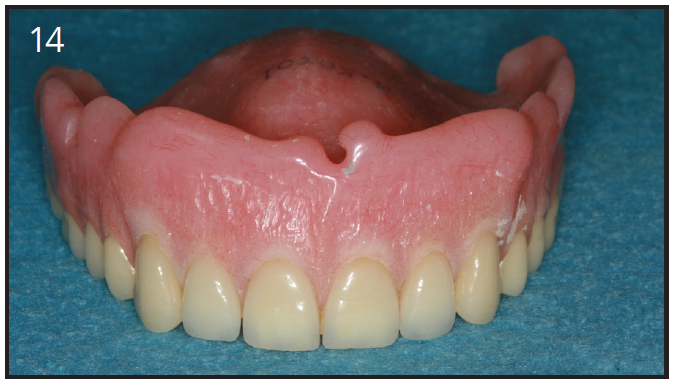

Since the maxillary arch is wider than the lower arch, and the bone in more porous, we need 4 to 6 implants for an overdenture. The advantage of having an implant-supported overdenture in the maxilla is that the palatal area can now remain uncovered. Having the palate open to the taste buds allows for an enhanced sense of taste. The overdenture can be removed by the patient and allows for thorough cleaning. Furthermore, it can give better lip support for patients who have lost bone in the anterior area, as compared to a fixed implant prosthesis. To restore the lip support, a flange is often necessary or extensive amount of bone grafting. We cannot attach a flange onto a fixed bridge because the patient will not be able to clean under it. (Figure 14)

Figure 14 – Overdenture with flange to restore lip support

Figure 14